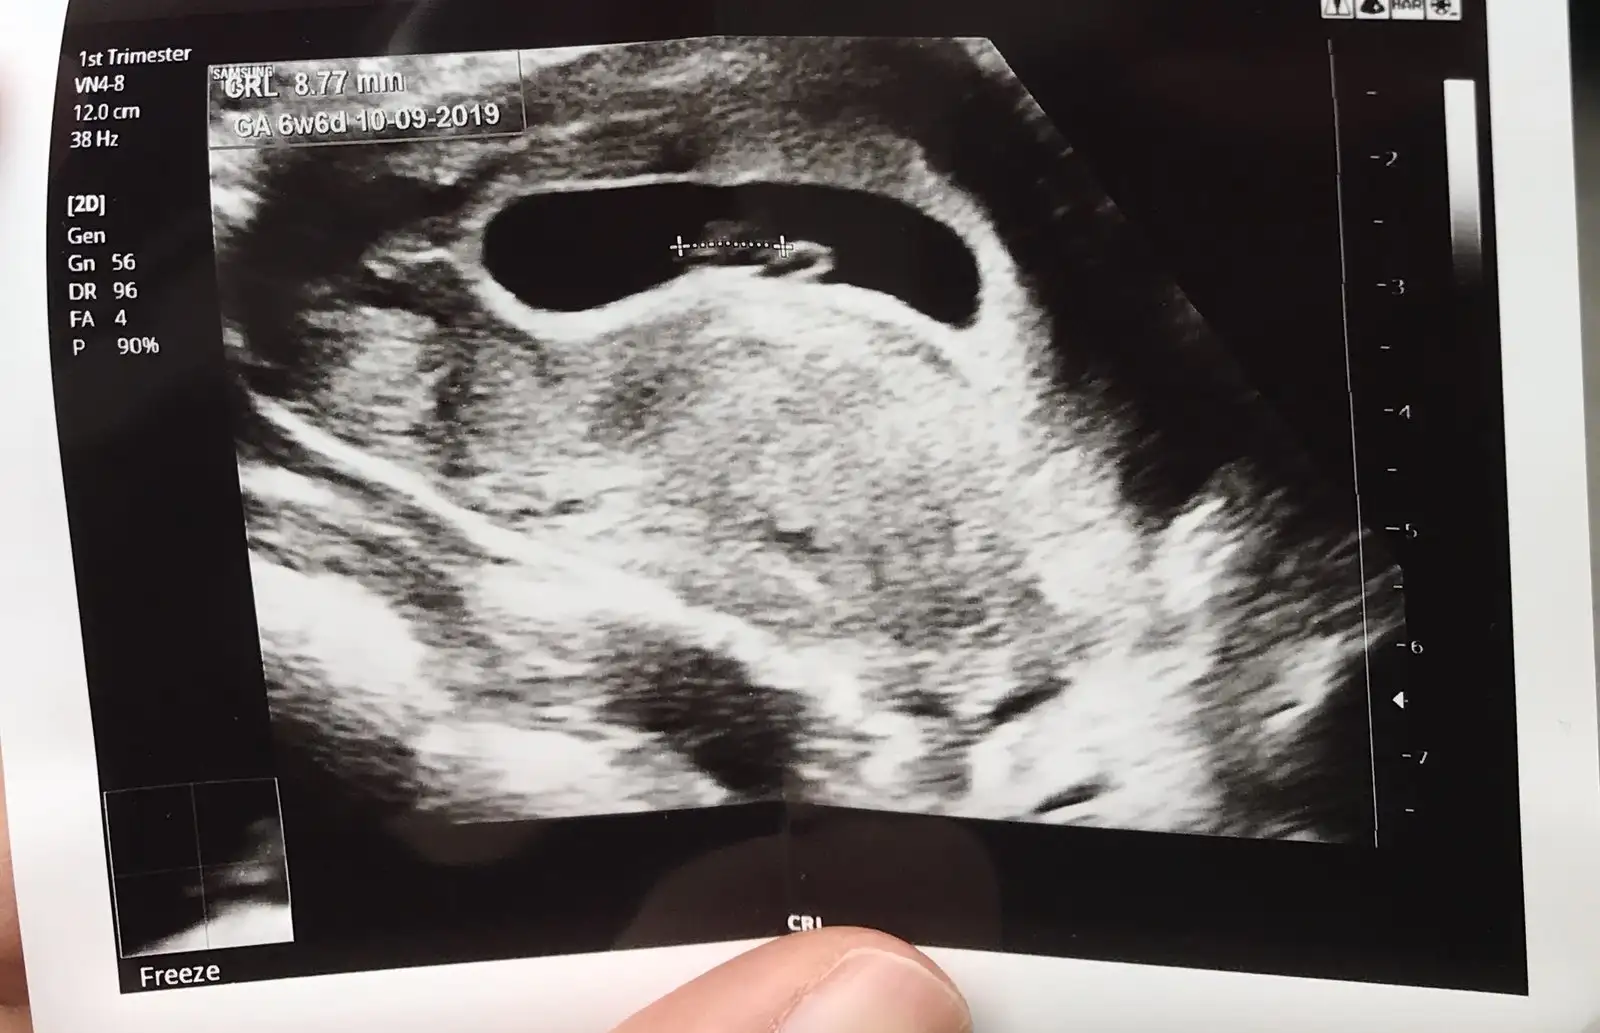

Benimde 6 7 haftalıkken kese görüntüsü tahmin edermisiniz cinsiyetini?

Eklentiler

• 1548419951174-657122974.webp

1548419951174-657122974.webp

36,9 KB · Görüntüleme: 90